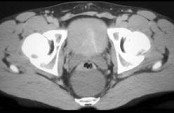

- 单项选择题男,21岁, 下腹部一囊性肿块,无压痛, 请结合图像,选择最可能诊断  (    )

- A、盆腔脓肿

- B、结肠重复畸形囊肿

- C、神经纤维瘤

- D、神经鞘瘤

- E、间质瘤